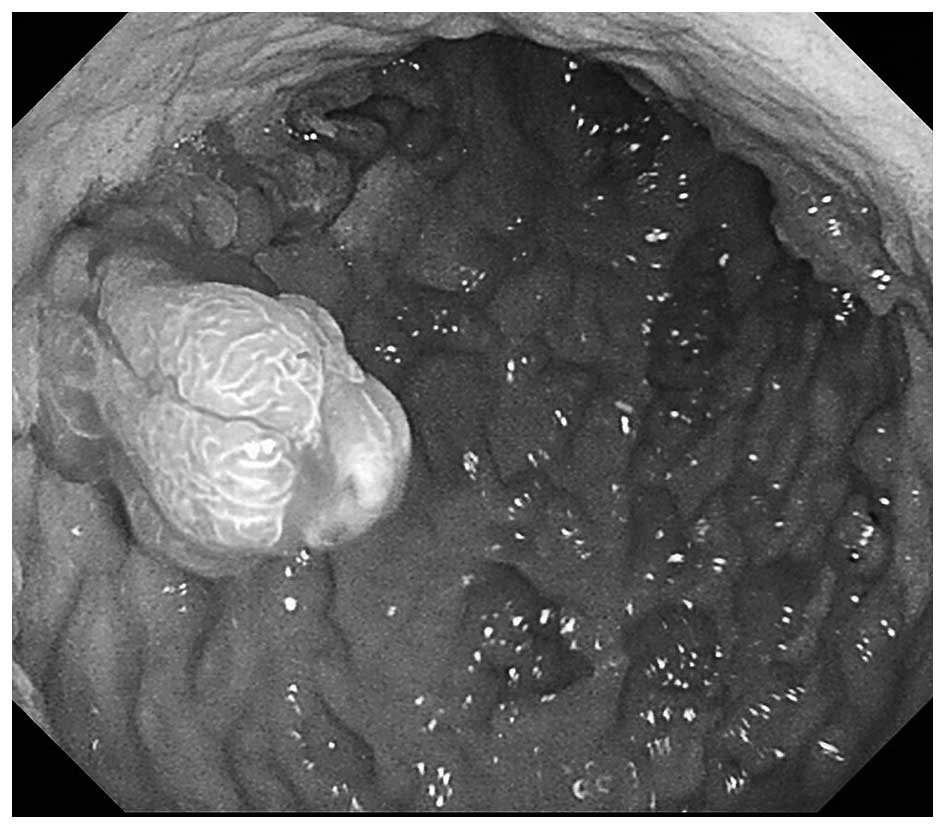

A 24-year-old man with an unremarkable medical history was referred to Onomichi General Hospital (Hiroshima, Japan) as a result of melena and anemia in 2004. An upper gastrointestinal endoscopy in 2004 revealed multiple edematous polyps around the fundus of the stomach (Fig. 1). Histological examination revealed a hyperplastic and disorganized foveolar epithelium, and an edematous lamina propria with infiltration of inflammatory cells, and the histological diagnosis was hyperplastic polyps. The patient began taking a proton-pump inhibitor and iron supplements, and he underwent an upper gastrointestinal endoscopy annually. The polyps appeared around the fundus in 2004 and had gradually progressed to the entire stomach in 2014 (Fig. 2). The number and size of the polyps had also increased. Endoscopic mucosal resection was performed frequently due to bleeding from the polyps. It was difficult to control the progressing anemia by non-surgical treatment, and, in 2014, histological examination revealed for the first time that the benign polyps were adenocarcinoma. Surgical treatment was therefore performed. At the time of surgery, the patient was 171 cm tall and weighed 62.5 kg. No skin lesions or loss of hair, which is characteristic of Cronkhite-Canada syndrome, was exhibited. Laboratory data demonstrated mild anemia (hemoglobin, 9.6 g/dl), but neither hypoproteinemia nor elevation of tumor markers, including carcinoembryonic antigen and carbohydrate antigen 19–9 was observed. With respect to the patient's family history, the patient's mother had succumbed to colon cancer in her 50s and his cousin had succumbed to an unknown primary cancer in his 30s. Colonoscopy revealed no specific findings. Enhanced computed tomography revealed that the stomach wall was edematous with enhanced thickening from multiple polyps (Fig. 3). An upper gastrointestinal series revealed that multiple polypoid lesions were limited to the entire stomach and were not present in the small intestine (Fig. 4). The patient underwent laparoscopy-assisted total gastrectomy with Roux-en-Y esophagojejunostomy. The resected specimen revealed numerous diffuse polyps throughout the entire stomach (Fig. 5). Microscopic findings revealed a hyperplastic and disorganized foveolar epithelium with an atypical nuclear shape. Enlargement of the nucleolus was also observed, and the patient was diagnosed with well-differentiated adenocarcinoma. A total of three lesions of early gastric cancer, and no lymph node metastasis were detected. Immunohistochemical staining revealed that the specimen was positive for p53 and carcinoembryonic antigen and exhibited a high index of mindbomb E3 ubiquitin protein ligase 1 (Fig. 6). The postoperative course was uneventful, hemoglobin level returned to the normal range, and the patient experienced no recurrence over a 1 year follow-up.

Figure 2.

Upper gastrointestinal endoscopy in 2014. An upper gastrointestinal endoscopy from 2014 revealed that the number and size of the polyps had increased.